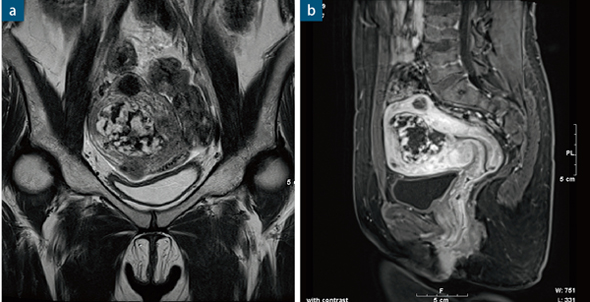

●症例8 絨毛性疾患(39歳,女性)

空間分解能の実用性に加え,dynamic studyにおける病変部と正常部のコントラストがついた画像は,診断に有用である。

a:TSE,T2強調コロナル像:TR/TE:4500/91,スライス厚:4mm,マトリックス:448×448,撮像時間: 1分52秒

b:Dynamic,TR/TE:4.0/1.5,スライス厚:2mm,マトリックス:320×270,撮像時間:32秒